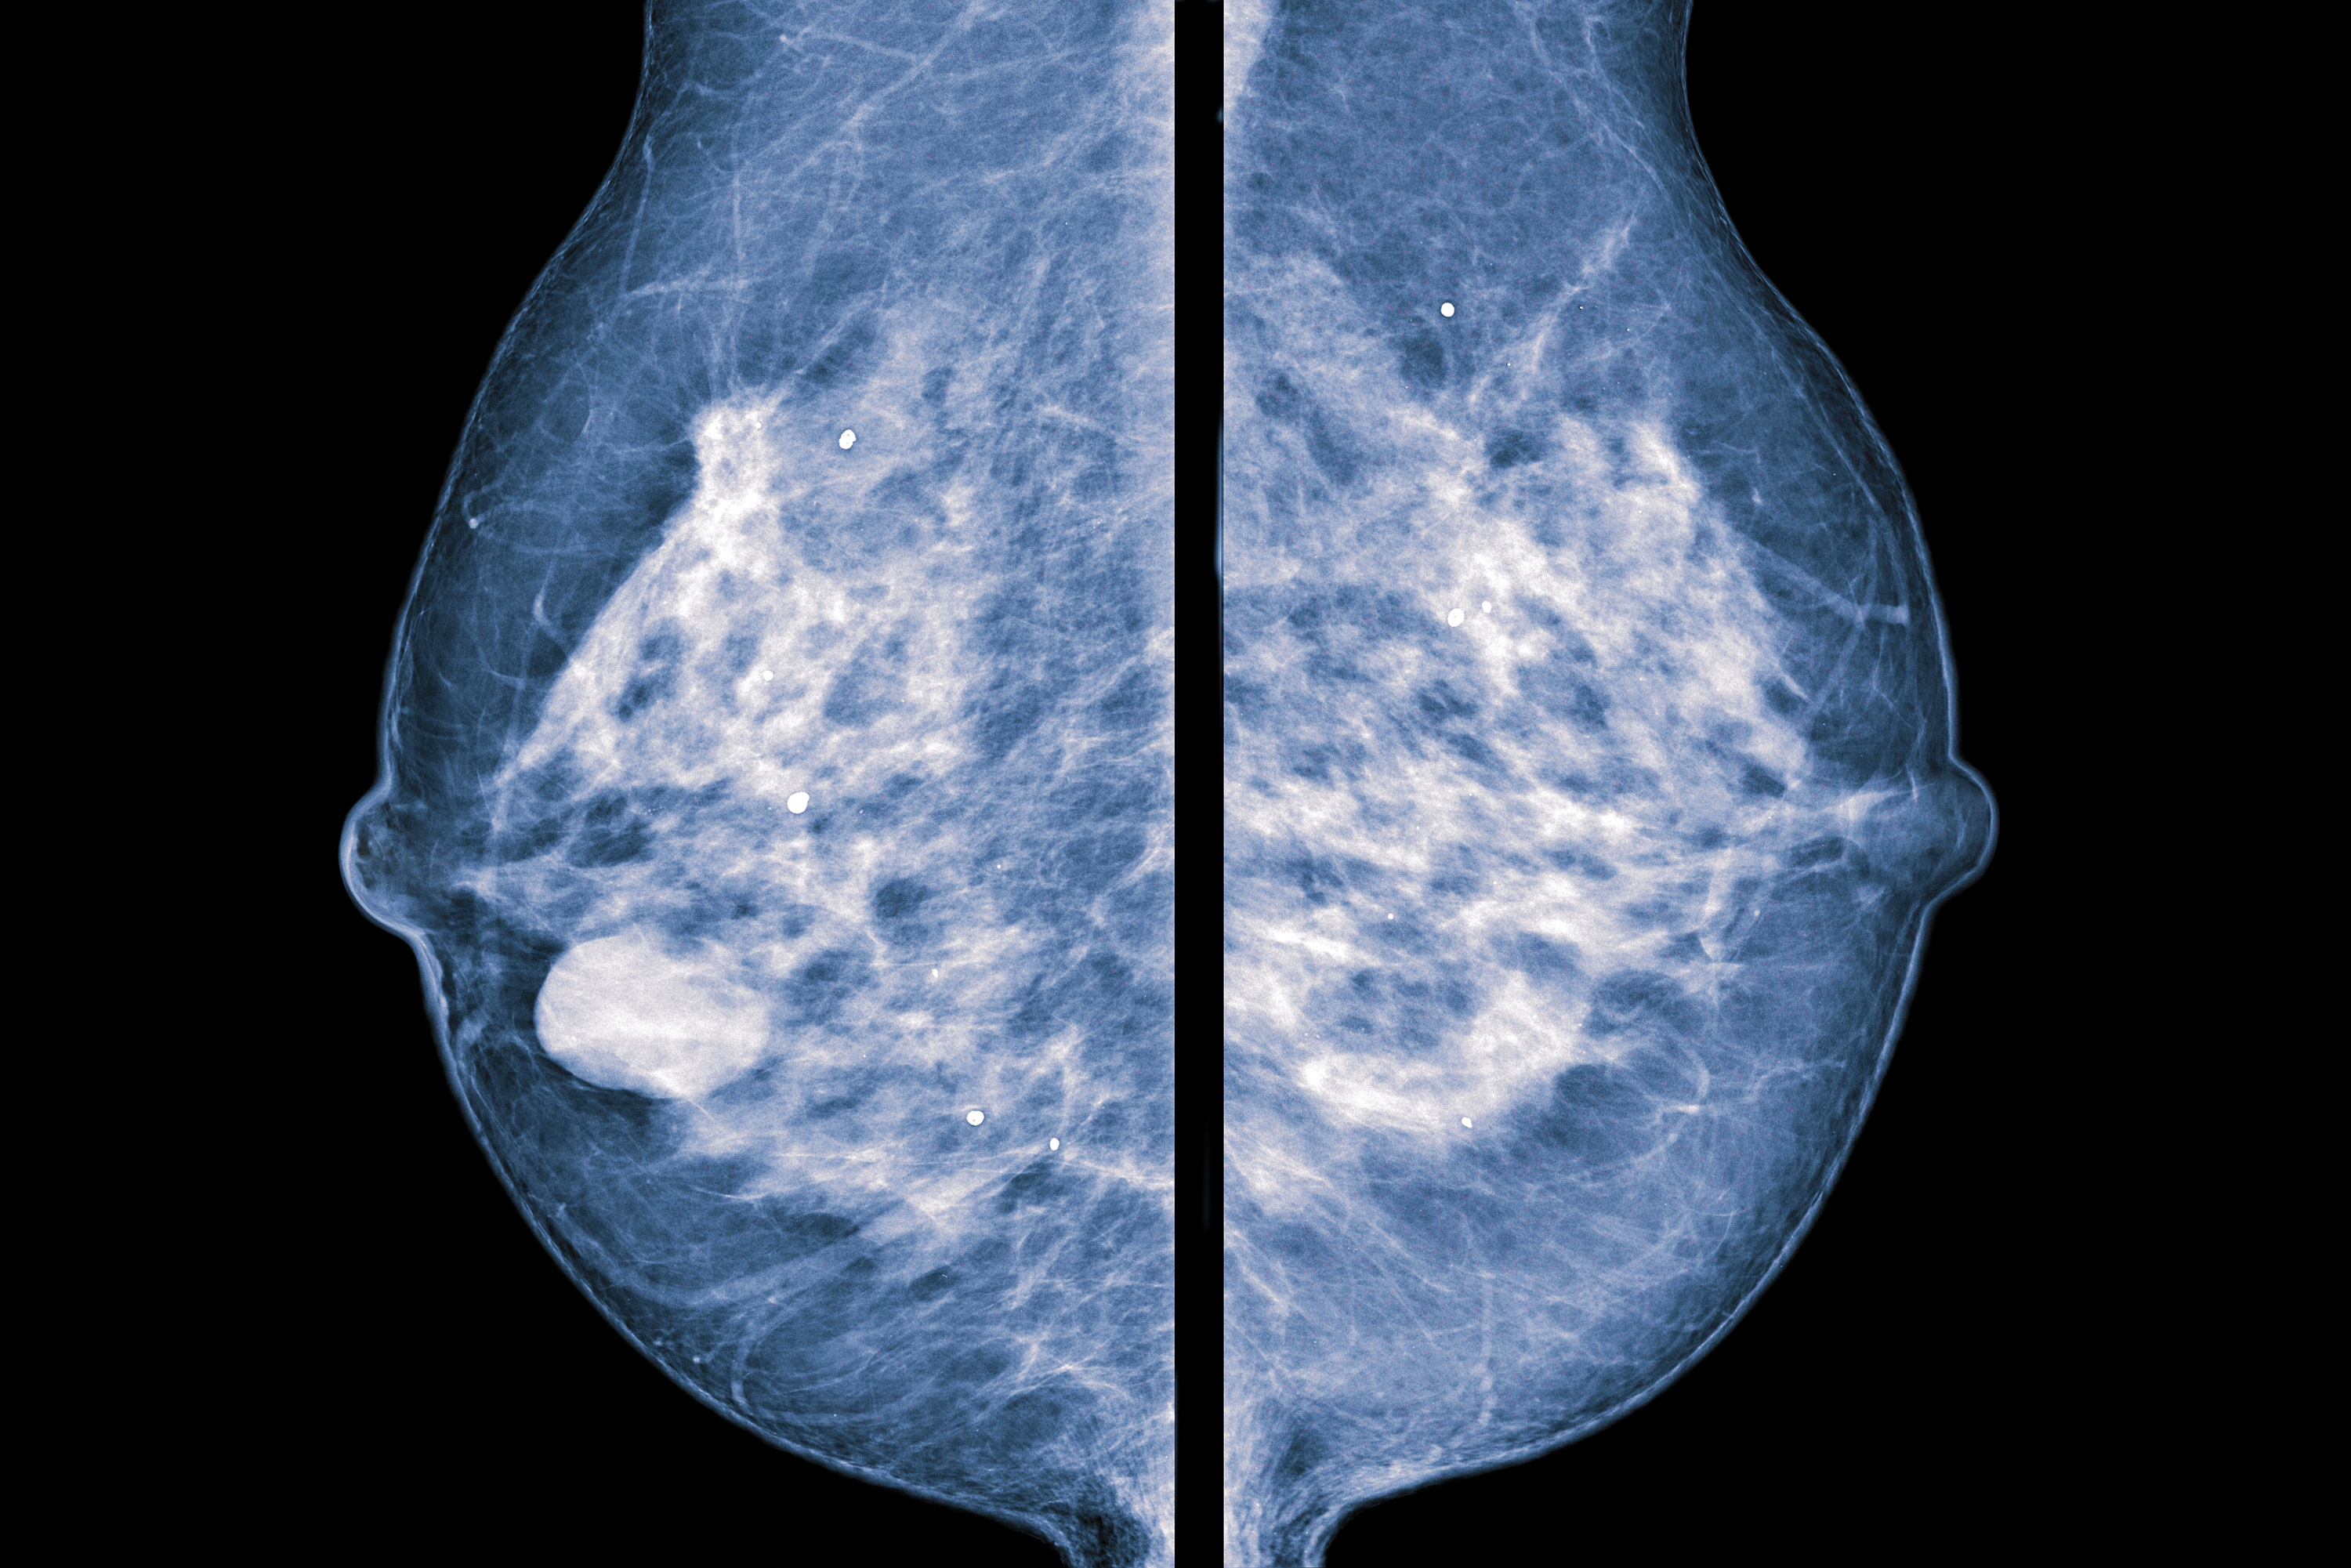

How can i prevent breast calcifications? The calcium is stored in our bones. You can’t prevent breast calcifications, but early detection through a mammogram is important in identifying any possible cancer that could.